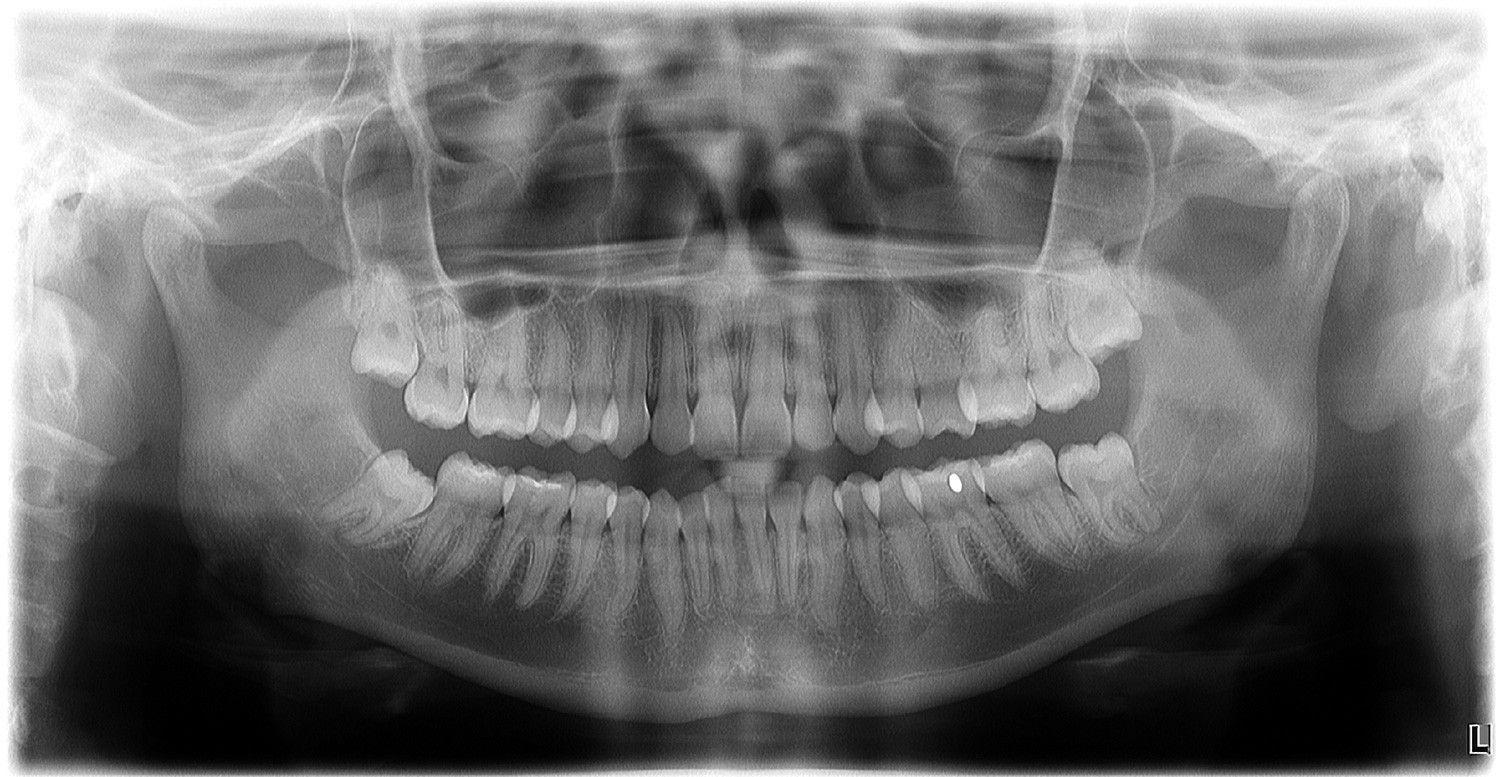

X-Rays have saved and improved millions of lives, but it is important to understand the dangers of excessive radiation. At McCall Family Dentistry, we used digital X-Rays. These produce sharp, clear images that Dr. Ryan can instantly view. These improve our diagnostic ability and allows for a quicker, more comfortable experience for our patients.

Panoramic: 80

Panoramic: 15